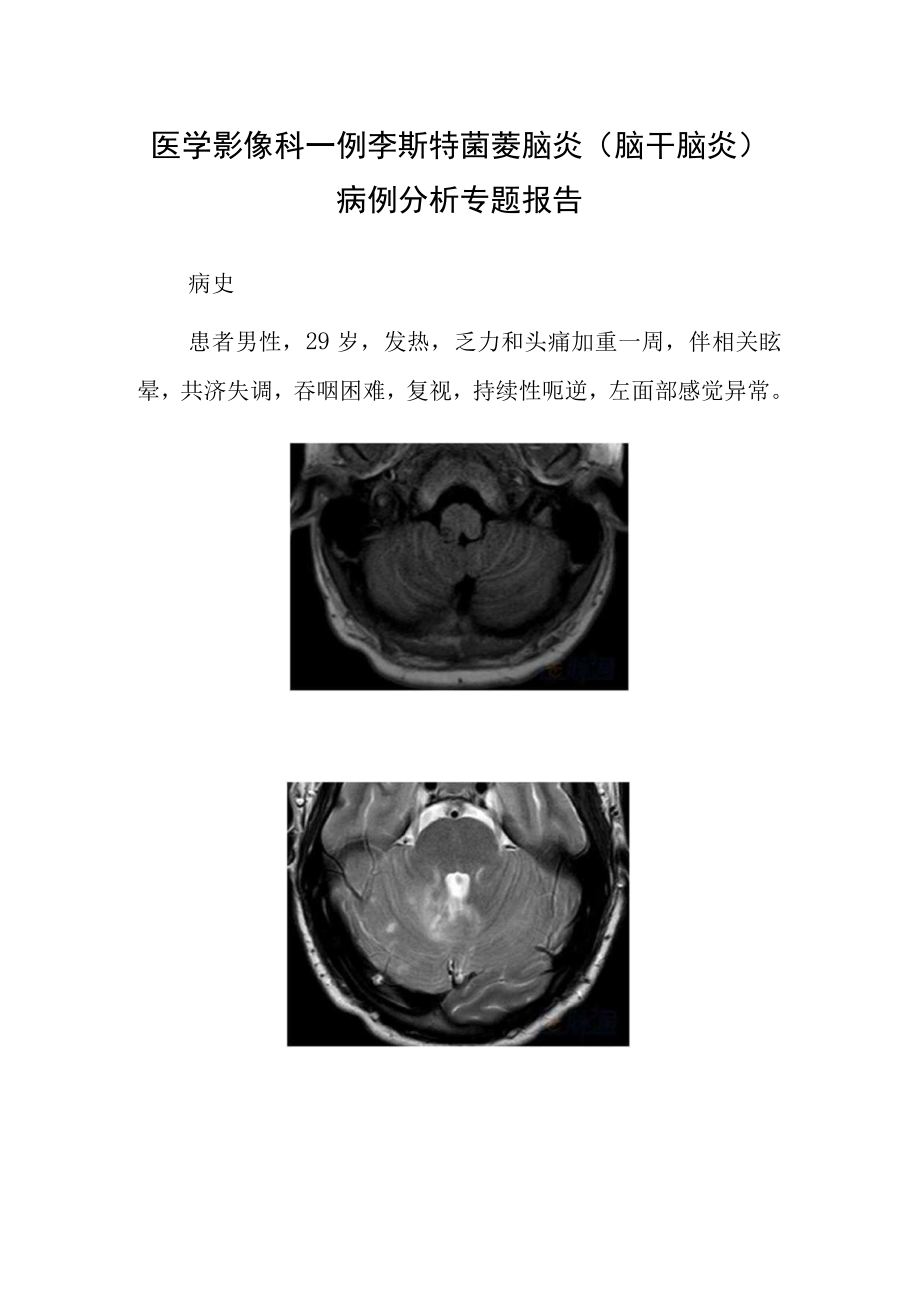

1、医学影像科一例李斯特菌菱脑炎(脑干脑炎)病例分析专题报告病史患者男性,29岁,发热,乏力和头痛加重一周,伴相关眩晕,共济失调,吞咽困难,复视,持续性呃逆,左面部感觉异常。读片分析轴向T1.WI(A)显示右延髓结节性Tb低信号病变。轴向T2WI(B,C)显示蚓部和两个小脑半球双边斑片状假结节性T2高信号。对比增强饱和脂肪TIW1.(D,E)显示脑干和小脑多发结节状和环状增强病变。左小脑半球也可见脑膜强化片状区域。轴向DWI(F)显示右侧延髓背索局限性扩散。诊断:李斯特菌菱脑炎(脑干脑炎)李斯特菌病是进食受李斯特菌污染的食品引起的一种严重感染。这种细菌可见于各种食物,如生肉,蔬菜和未经高温消毒牛奶